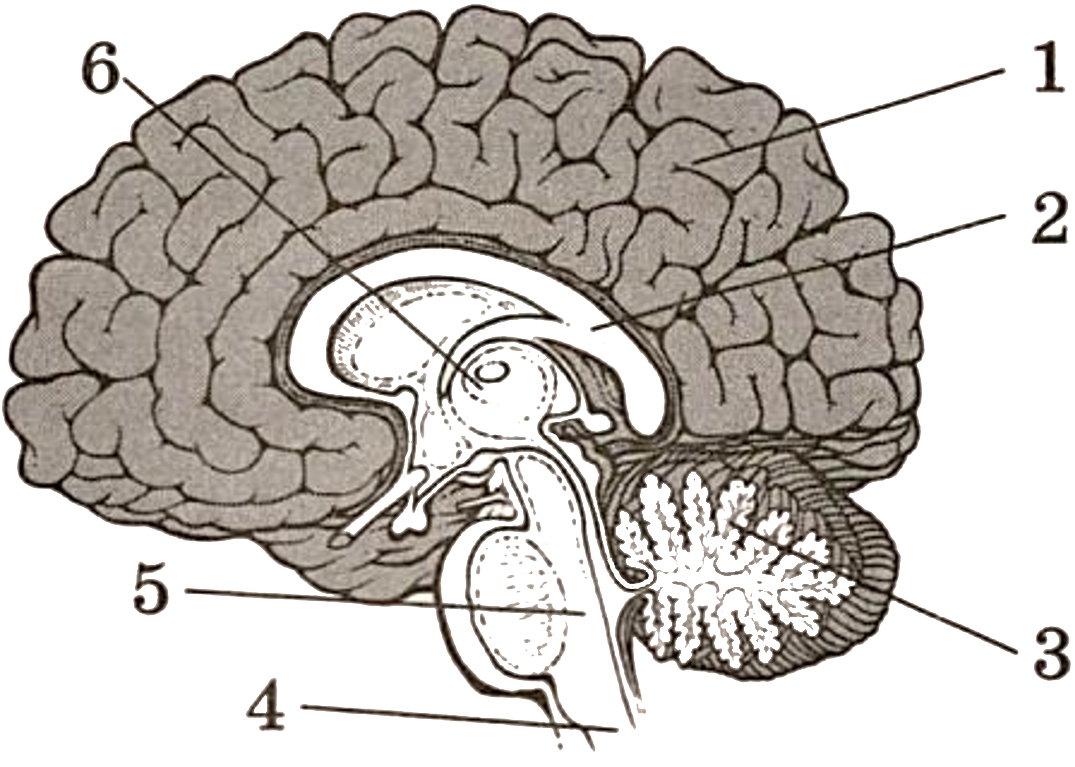

Легкие рисунки головного мозга: Пошаговые инструкции

Раздел: Житейские мотивы